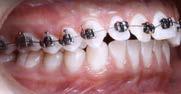

Se describe un caso de un paciente masculino de 18 años de edad, con diagnóstico de clase II esquelética, normodivergente, clase II canina y molar bilateral, overjet aumentado, laterales microdónticos, apiñamiento leve superior e inferior, asimetría facial, canteamiento oclusal y con hábito de deglución atípica. Objetivos: mejorar el perfil facial, corrección del apiñamiento maxilar y mandibular, del overjet y overbite y de las líneas medias dentales, así como la obtención de clase I molar y canina bilateral. Generar remodelación condilar a largo plazo, corrección de hábito, lograr correcta intercuspidación, lograr guía de desoclusión canina, lograr guía incisiva, gingivectomía, exodoncias de terceros molares 18, 28, 38 y 48 y restauración de incisivos superiores 11, 12, 21 y 22. Tratamiento: alineación, nivelación, avance mandibular, stripping, detallado y retención. A través de brackets prescripción Roth 0.022 x 0.028”, tubos bondeables en primeros y segundos molares y bite ramps angulados en incisivos centrales superiores 11 y 21. El tiempo activo de tratamiento fue de 1 año y 4 meses, la retención se llevó a cabo mediante retenedores circunferenciales con cinturón vestibular en ambas arcadas y un Frankel unilateral izquierdo de uso nocturno.

Tratamiento

alineación y nivelación haciendo uso de la técnica de bondeado indirecto (Figura 9 y 16) con secuencia de arcos CuNiTi 0.016” superior, NiTi 0.016, 0.016” x 0.022”, 0.017” x 0. 025” y acero inoxidable 0.018”.

La obtención de clase I canina y molar bilateral se obtuvo mediante el avance mandibular y uso de elásticos intermaxilares con el uso de bite ramps en 11 y 21 angulados largos, elásticos clase II cortos y largos de 3/16” 4.5 oz sencillos y dobles figura 10 y elásticos clase II continuos en W de uso nocturno de 5/16” 2.5 oz (Figura 1). La corrección del overjet y overbite se alcanzó con anclaje mínimo, elásticos intramaxilares, IPR, rebondeo y arcos seccionales mediante ferulizado con ligadura metálica de segundo molar superior derecho 17 a canino superior derecho 13 y de lado contrario de 27 a 23, tie back inferior, stripping de 33 a 43, cadena de canino a canino superior de 13 a 23 y de primer molar a primer molar inferior de 36 a 46, “Storino Leash" anteroinferior de 33 a 43, rebondeo con alturas Pitts en anterosuperior y arcos seccionales de NiTi 0.016”. Máxima intercuspidación, paralelismo radicular y